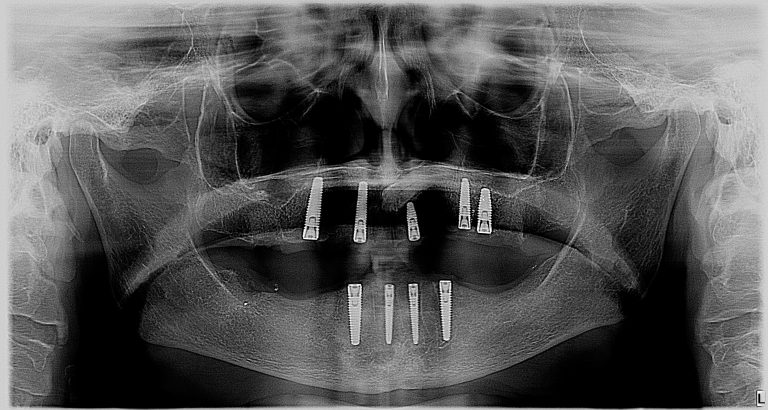

This is a wonderful case of a patient who had broken teeth for a very long time. The outcome is a supported set of full dentures on implants. The patient does not experience movement of teeth and has the ability to eat all food. The implant supported denture allows the patient to have a very high biting force, which is very important when you want to eat crunchy fresh fruits and vegetables. This was a fully guided case.